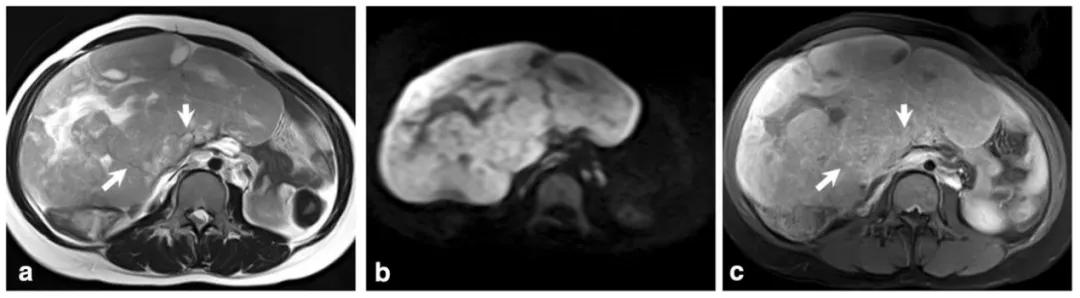

女,75 岁,浆液性癌。CA-125 升高。双侧卵巢不规则肿物,与腹膜结节分界不清,T2WI 呈不均匀稍高信号(图 a),DWI 呈不均匀高信号(图 b),CT 显示肿物内钙化(图 c)。箭头显示左侧髂血管旁转移淋巴结。